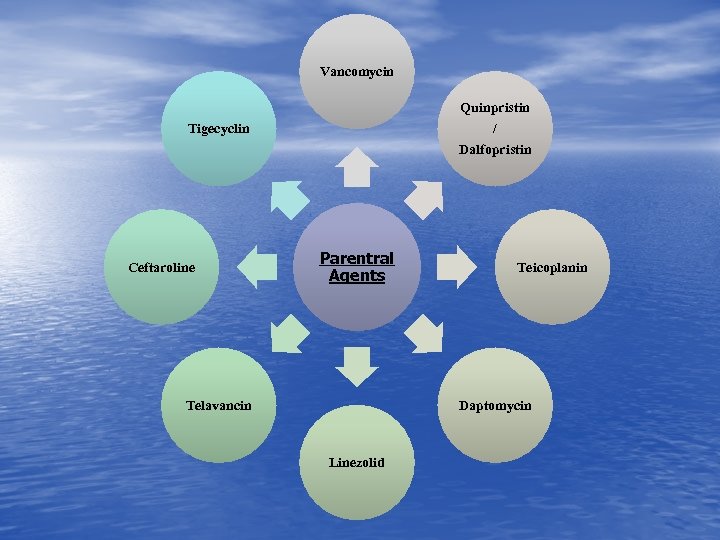

Vancomycin Quinpristin / Tigecyclin Dalfopristin Ceftaroline Parentral Agents Telavancin Teicoplanin Daptomycin Linezolid

Vancomycin Quinpristin / Tigecyclin Dalfopristin Ceftaroline Parentral Agents Telavancin Teicoplanin Daptomycin Linezolid